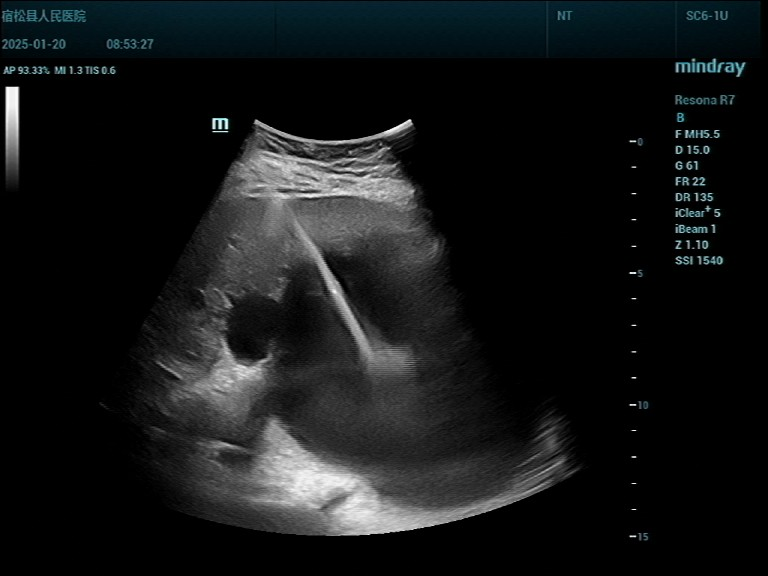

手术中,经超声精确定位,局部麻醉,有丰富介入与穿刺经验的吴飞医生和杨翠桥护士熟练操作配合,穿刺引流管精准到位,抽出20ml囊液做蛋白定性试验(+),囊内注入造影剂、超声造影显示囊肿与肝内胆管不相通,由于囊肿过于巨大,一次抽完对身体不利,计划分多次引流,总共引流量达1000ml,再用硬化剂冲洗囊腔,使囊壁纤维化不再分泌囊液而达到治疗目的。

▲1.治疗前超声显示 ▲2.穿刺针经皮肝进入囊肿内

▲3.超声实时监测穿刺导丝、引流管进入囊肿,安全可靠 ▲4.抽出20ml囊液行蛋白定性实验(+)